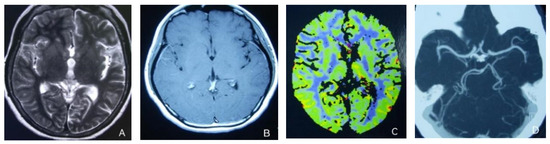

At the age of 51, she had a migraine attack with weakness in the left limb. The headache became increasingly serious, so she was admitted to a hospital six days after the attack. Upon admission, she had severe headaches and left limb weakness, and the neurological examination revealed left hemiparalysis with muscle strength at 3/5 by manual muscles testing (MMT). A brain MRI (magnetic resonance imaging) on day two of admission revealed cortical swelling in the right cerebral hemisphere (Figure 1A), and on the day three of admission, the magnetic resonance angiography (MRA) showed a slight decrease in the branches of the left middle cerebral artery (MCA). The main trunk of the left posterior cerebral artery (PCA) was slender contralateral, and its branches were significantly reduced contralaterally (Figure 1B). Symptoms persisted. On day five of admission, the patient had a focal epileptic seizure, which was followed by two more seizures. Subsequently, the patient’s left limb weakness gradually worsened, the neurologic examination revealed left hemiparalysis with muscle strength at 0/5 by MMT, and she gradually developed unconsciousness to light coma. Brain CT scans during coma revealed swelling of the right cerebral cortex (Figure 1C). Contrast-enhanced brain MRI showed swelling and diffuse enhancements in the cortex of the right cerebral hemisphere (Figure 1D). Perfusion-weighted imaging (PWI) showed right hemisphere hyperfusion (Figure 1E). Based on her medical history and presentation at admission, a lumbar puncture was performed, and the cerebrospinal fluid pressure (CSF) was 204 mm H2O. The biochemical and cytologic examination of the CSF revealed normal chloride, glucose and cell counts and classifications, in addition to normal protein levels. The CSF tested negative for bacteria, viruses, fungi and autoimmune encephalitis. Whole-exome sequencing showed a missense mutation (c.2473G > A, p.Glu825Lys) in exon 18 of ATP1A2. Based on a series of tests, the patient was diagnosed with FHM2 caused by a pathogenic ATP1A2 mutation. During hospitalization, we dehydrated the patient, gave the patient paracetamol for symptomatic treatment and an intramuscular injection of phenobarbital to control seizures. On the 15th day after admission, consciousness and hemiplegia improved, and the headache was relieved; the patient was discharged after 22 days. She was back to normal, and at later follow-up, the patient’s brain MRI (Figure 2A), contrast-enhanced brain MRI (Figure 2B), PWI (Figure 2C) and computed tomography angiography (CTA) all returned to normal (Figure 2D). The time course diagram of the disease in our patient is presented in Figure 3.

Figure 2.

(A,B) Previously demonstrated the swelling of cerebral cortex has resolved; (C) hyperfusion in the right hemisphere has returned to normal. (D) Bilateral MCA and PCA were relatively symmetrical.